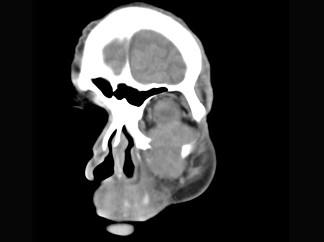

男,65岁,左眼球突出近一年,鼻涕带血,面颊部隆起,同时面颊部有麻木感,CT检查如图,最可能诊断为 ( )